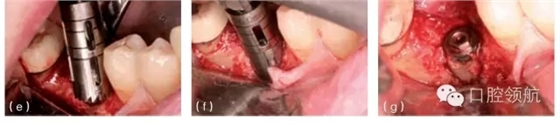

圖10.4 (a)在頜骨模型上,環(huán)鉆置于種植體上。環(huán)鉆是空心柱狀的,鉆的末端有切割螺紋。它放在種植體上,可以順著種植體邊緣周的骨組織的切線方向環(huán)行去除骨組織,從而使種植體移除造成的創(chuàng)傷減到最小。(b)種植單冠的頰面觀,種植修復(fù)后患者產(chǎn)生持續(xù)性的疼痛,且無(wú)法緩解,需要取出種植體。(c)根尖片顯示種植體正常。(d) 取出牙冠,翻瓣暴

露種植體。(e)用環(huán)形鉆取出包繞種植體的骨環(huán)。(f)環(huán)形鉆包繞種植體,環(huán)形切削達(dá)種植體全長(zhǎng)。(g)環(huán)形鉆切削完畢,(環(huán)形鉆中心的)切除的骨組織包繞種植體,種植體周圍已被分離,只有根尖區(qū)還有骨組織與種植體相連接。將使用一種器械,置于骨環(huán)周,切斷根尖區(qū)的骨組織。(h)包含種植體在內(nèi)的骨環(huán)被取出。(i)取出后置于外科盤上,可見(jiàn)種植體及附著周圍薄層的骨組織。種植體植入時(shí)曾植骨,種植體周可見(jiàn)殘留的顆粒狀的骨移植材料。(j)種植體移除后,去骨創(chuàng)面的牙合面觀。(k)將骨移植材料(同種異體骨與異種骨移植材料混合)放置在去骨創(chuàng)面中。(l)放上屏障膜,用釘固定。